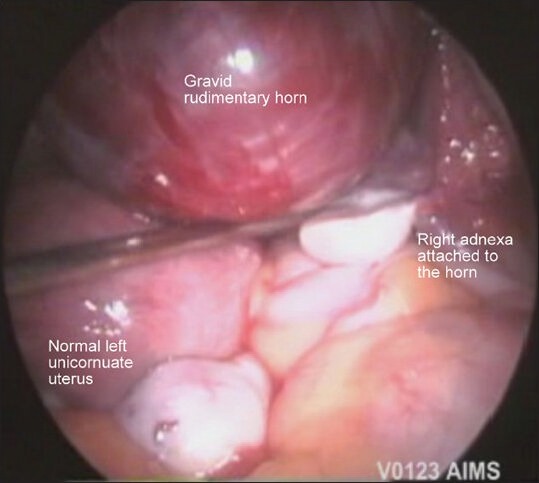

A non-communicating rudimentary horn is an uncommon site for ectopic pregnancy. Rudimentary horn pregnancy (RHP) is a rare entity but associated with grave clinical consequences. Majority of these cases if not detected timely end up in uterine rupture and present as an obstetrical emergency. We present this case of a 32-year-old, third gravida with a 12 weeks live gestation in the right rudimentary horn, which was successfully managed with laparoscopic resection. Early diagnosis is the key stone in the management of such cases. Laparoscopic resection is a safe and viable option in the surgical management of unruptured RHP.